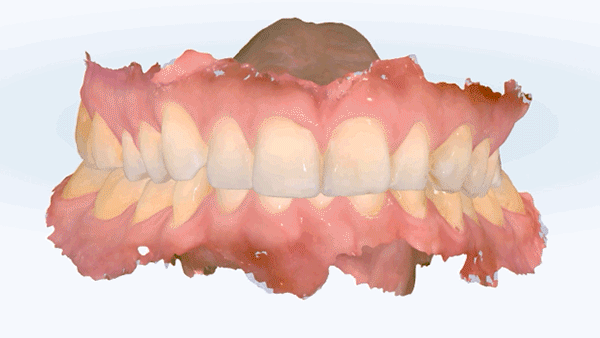

Her smile already had a beautiful smile arc—the curve connecting her upper front teeth followed the contour of her lower lip perfectly. She was satisfied with her overall appearance, but wanted to correct the slight size difference and minor misalignment between her two front teeth to make them look more even.

Upon examination, her left central incisor was slightly larger than the right, and there was mild crowding in both upper and lower anterior teeth. She had previously undergone extraction orthodontics—her lower first premolars had been removed, leaving a small gap on the right side. In addition, due to deep overbite, her lower front teeth were barely visible. She also had a dental implant on her lower left first molar, while the second molar was missing.

To comprehensively correct all these issues, full-mouth re-orthodontic treatment would have been ideal. However, considering her limited time and preference for minimal intervention, we discussed two treatment options focused only on improving the alignment of her upper front teeth: